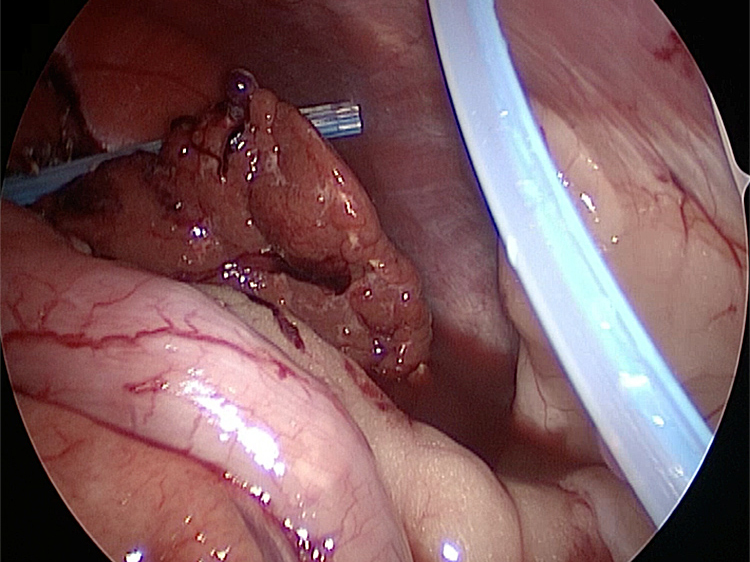

摘出した胆嚢にはゼリー状の胆泥がへばりついていました。

摘出した胆嚢はカチカチで中にはゼリー状の硬い物質が詰まっていました。

胆嚢は分厚くなり周りには脂肪が張り付いていました。手術をして元気になりました。